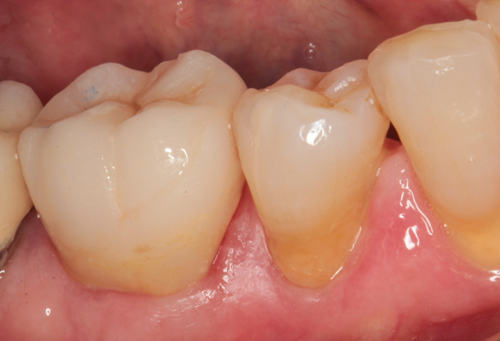

The crown and printed model were returned to my office. At the seating appointment, the provisional crown was removed and the final crown was tried in. Contacts, margins and occlusion were evaluated and no adjustments were needed. The crown was bonded to place using a self-adhesive resin cement (Fusion-ZR Dual Cure Resin Cement, Taub Products). It can be seen in place from the facial view in Figure 11 and the occlusal view in Figure 12. The radiograph in Figure 13 shows the excellent fit of the digitally fabricated crown.

Fig. 11 Fig. 12 Fig. 13